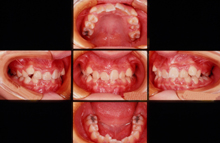

・CASE 3 ~ 受け口 ~

治療前 11歳4ヶ月

治療後 12才2ヶ月

治療後 10年後 24歳6ヶ月

CASE 3 ~受け口~ 上下の歯が反対咬合でよく噛めない。

治療前(初診時年齢)11歳4ヶ月の女児

物が噛みきれない

マルチブラケット装置(表側ワイヤー装着)永久歯を抜かずに治療しました

治療後 12歳2ヶ月 治療期間8ヶ月 治療費700,000円

副作用とリスク(一時的な顎関節の痛み、歯の痛み、歯が磨きにくい、口内炎、しゃべりづらい、歯根吸収、歯肉退縮、後戻り、治療期間について説明しました。)

保定終了後 8年3ヶ月 24歳6ヶ月